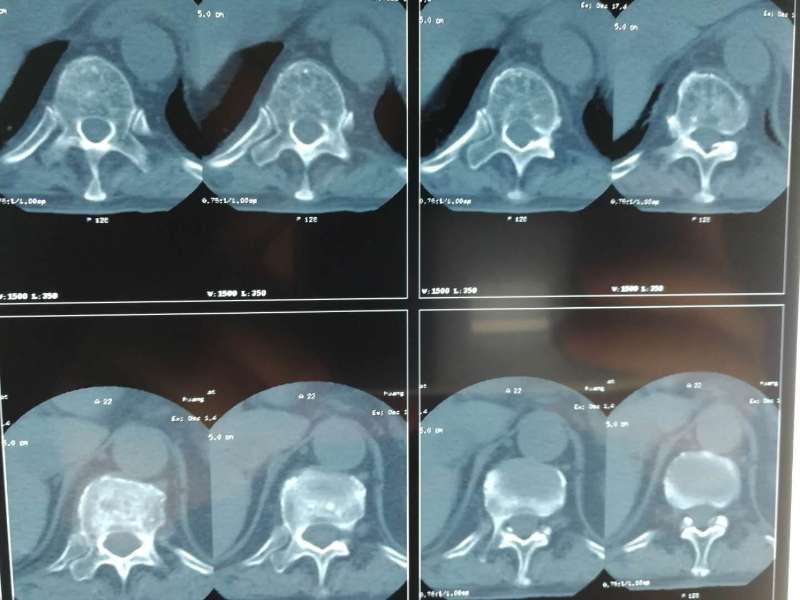

4月10日,黄阿姨在家人的搀扶下,来到该院外二科,经门诊医生查阅病史、查体后,以“腰4椎体压缩性骨折”之诊断收住入院。入院时黄阿姨腰部剧痛,活动受限,卧床翻身受限,站立及坐立困难,日常生活起居受影响,生活质量严重下降。黄阿姨被病痛折磨的苦不堪言,请求尽快手术治疗,力争早日开始正常生活。

急切想步入正常生活,这是医患之间的共同目标,但难题也同样摆在了该院外二科医师团队面前:患者高龄,切开复位手术风险较高,术后恢复较慢,且需行二次手术取出内固定,如果使用传统的手术方法,手术风险高且术后恢复较慢,且并发症较多,综合考虑后,决定行经皮椎体成形术。

做好各项术前检查后, 4月11日,在局部麻醉下行腰4椎体压缩骨折经皮椎体成形术,经过1个小时的精心手术,术后回到病房,黄阿姨诉腰部疼痛明显减轻,卧床翻身自如。